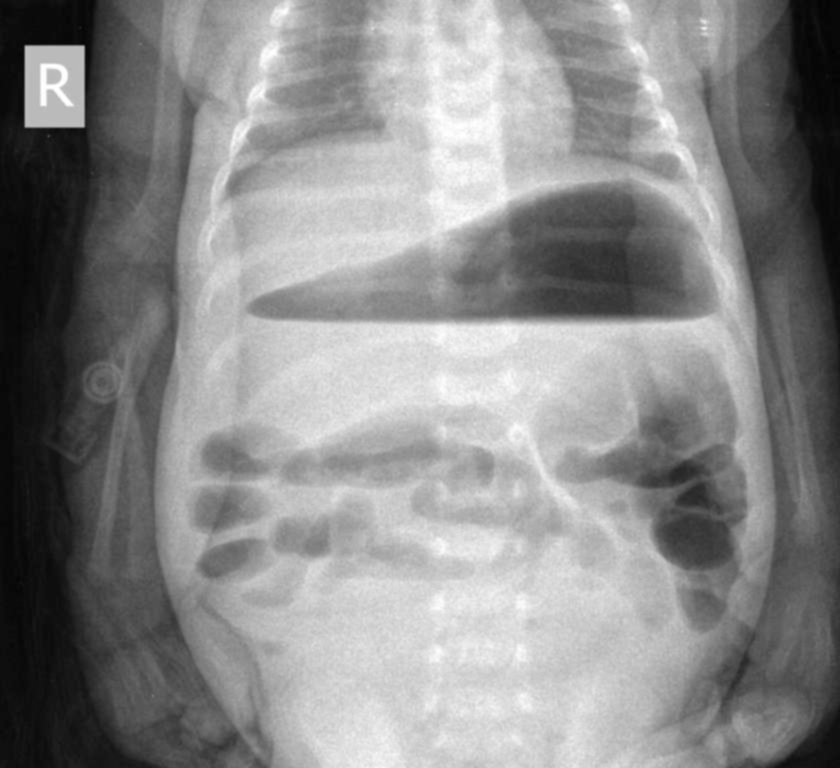

Пневматизация кишечника выражена что это

Пневматизация кишечника выражена что это 112 фотографий